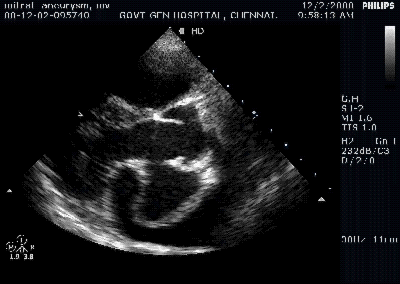

We have found, patients with DCM with mild mitral regurgitation tolerate excercise better than patients who have very competent and rigid mitral valve.It is presumed a mitral valve which gives in a little bit , decompresses the LV with a symptomatic benefit.But if the MR , is occurs in an eccentric path or it results in significant volume burden the potential advantage becomes a liability.